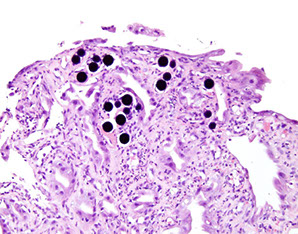

Clostridium ventriculi

Previously known as Sarcina ventriculi

- may be associated with gastric outlet obstruction such as in patients with diabetes

• Gram positive, anaerobic, sugar fermenting bacterium, S. ventriculi was first observed in the human stomach in 1842 by Goodsir . Readily found in soil and is known to cause a similar type of gastric injury in animals.

• Delayed gastric emptying and carbohydrate stasis in association with acidic gastric juices may provide an ideal culture medium

• Studied patients all had underlying delayed gastric emptying (one

had a bezoar) from diabetic neuropathy, narcotic use, and pyloric

stenosis secondary to malignancy

• The organism may simply colonize pre existing lesions but there

are too few cases to draw firm conclusions as to whether the

organism is truly a pathogen.

• Packets of 4, 8 or more cells with characteristic flattening

Clostridium ventriculi - assoc c gastric outlet obstruction